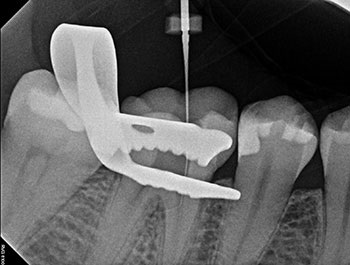

After the buildup and root-filling material were removed, a microscope was used to confirm that no cracks were present in the pulp chamber or the coronal third of the canals. This tooth was treated in multiple visits using calcium hydroxide, an antimicrobial intracanal medicament, and to confirm healing. The root canal system was cleaned, calcium hydroxide was placed, and a double-layered long-term provisional restoration made of Cavit and bonded composite were placed to seal the access preparation.

Fig. 2: Postoperative PA.